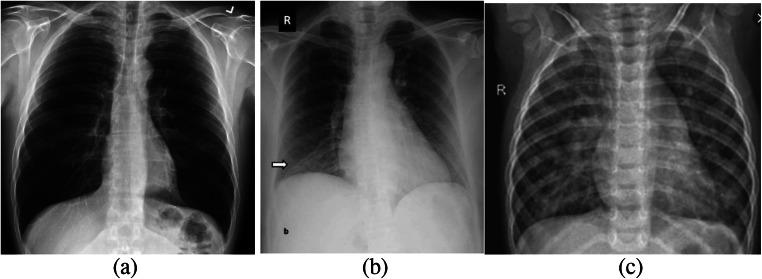

The quick spread of coronavirus disease (COVID-19) has become a global concern and affected more than 15 million confirmed patients as of July 2020. To combat this spread, clinical imaging, for example, X-ray images, can be utilized for diagnosis. Automatic identification software tools are essential to facilitate the screening of COVID-19 using X-ray images. This paper aims to classify COVID-19, normal, and pneumonia patients from chest X-ray images. As such, an Optimized Convolutional Neural network (OptCoNet) is proposed in this work for the automatic diagnosis of COVID-19. The proposed OptCoNet architecture is composed of optimized feature extraction and classification components. The Grey Wolf Optimizer (GWO) algorithm is used to optimize the hyperparameters for training the CNN layers. The proposed model is tested and compared with different classification strategies utilizing an openly accessible dataset of COVID-19, normal, and pneumonia images. The presented optimized CNN model provides accuracy, sensitivity, specificity, precision, and F1 score values of 97.78%, 97.75%, 96.25%, 92.88%, and 95.25%, respectively, which are better than those of state-of-the-art models. This proposed CNN model can help in the automatic screening of COVID-19 patients and decrease the burden on medicinal services frameworks.

冠状病毒病(COVID-19)的迅速传播已成为全球关注的问题,截至2020年7月,确诊患者已超过1500万。为了应对这种传播,临床成像,例如X光图像,可用于诊断。自动识别软件工具对于利用X光图像筛查COVID-19至关重要。本文旨在从胸部X光图像中对COVID-19患者、正常人和肺炎患者进行分类。因此,本文提出了一种优化卷积神经网络(OptCoNet)用于COVID-19的自动诊断。所提出的OptCoNet架构由优化的特征提取和分类组件组成。灰狼优化器(GWO)算法用于优化训练CNN层的超参数。利用一个公开可用的COVID-19、正常人和肺炎图像数据集,对所提出的模型进行了测试,并与不同的分类策略进行了比较。所提出的优化CNN模型的准确率、灵敏度、特异性、精确率和F1分数分别为97.78%、97.75%、96.25%、92.88%和95.25%,优于现有模型。所提出的CNN模型有助于自动筛查COVID-19患者,并减轻医疗服务系统的负担。